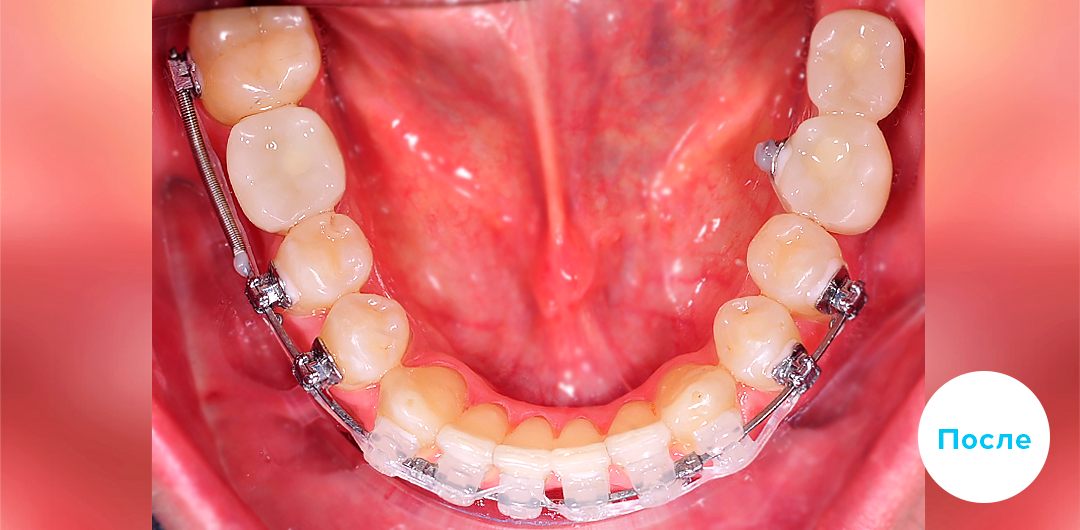

Результаты лечения